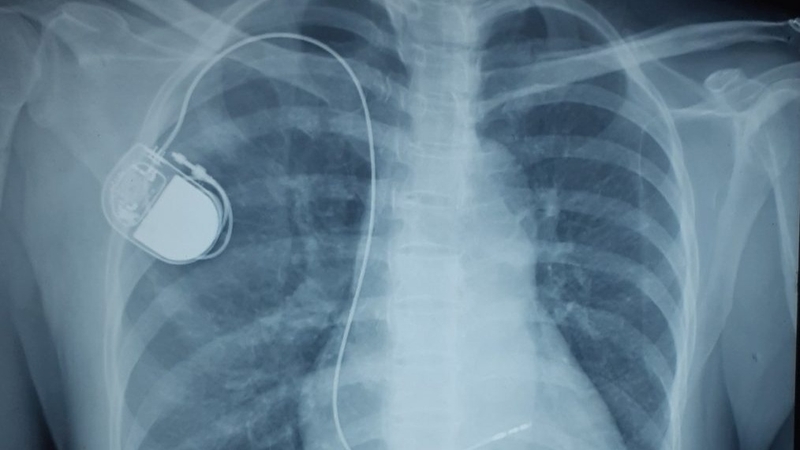

Sau khi chọc được tĩnh mạch, bác sĩ sẽ đưa dây điện cực vào buồng tim và nối nó với máy tạo nhịp tạm thời. Khi dây điện cực đã được đưa vào tim, bác sĩ sẽ theo dõi màn hình máy điện tâm đồ để đảm bảo rằng dây điện cực đã đặt ở đúng vị trí, thường là nằm gần thành tâm thất phải.

Sau khi đã cài đặt các thông số phù hợp cho máy tạo nhịp, bác sĩ sẽ tiến hành kiểm tra sau khi đặt máy. Các phương pháp kiểm tra bao gồm chụp X-quang ngực thẳng, đo điện tâm đồ, và siêu âm tim để nhìn thấy vị trí của điện cực trong tâm thất phải.